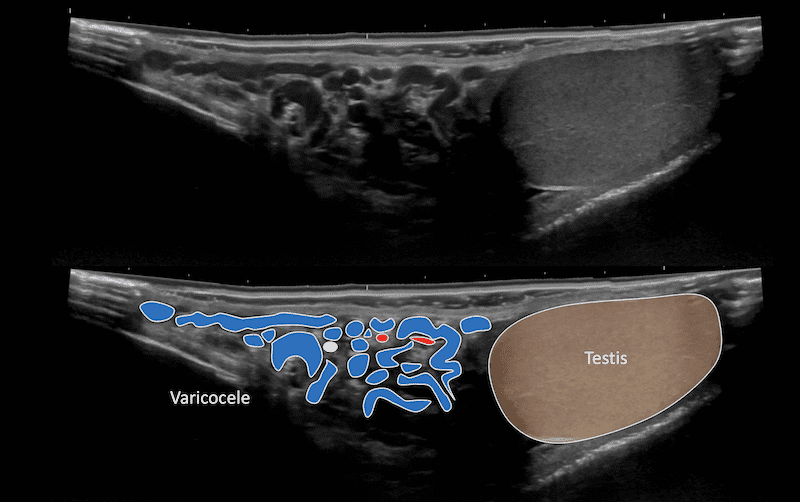

Immagine 2: Varicocele durante la manovra di Valsalva.

La manovra di Valsalva aumenta la pressione intra-addominale e c’è un breve reflusso attraverso le vene dilatate del plesso pampiniforme.